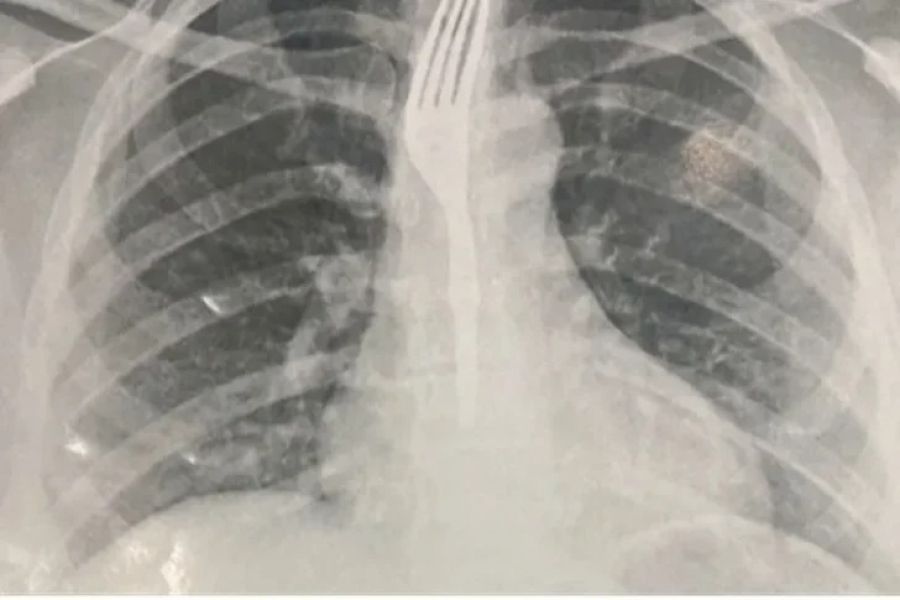

Ela deu entrada no Hospital Geral de Guanambi (HGG), onde exames de imagem apontaram que o objeto estava alojado no esôfago em posição de risco.